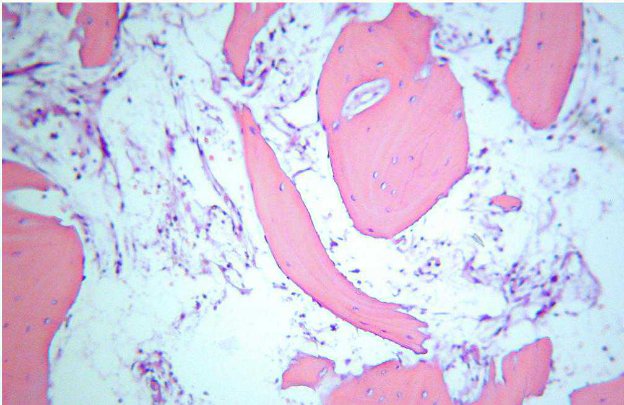

Come si osserva in figura 4, l’amputazione digitale prede, in fase di trimming, due passaggi:

Figura 4 - Margini a carico del dito (a sinistrasezioni dei tessuti molli, a destrasezioni post-decalcificazione).